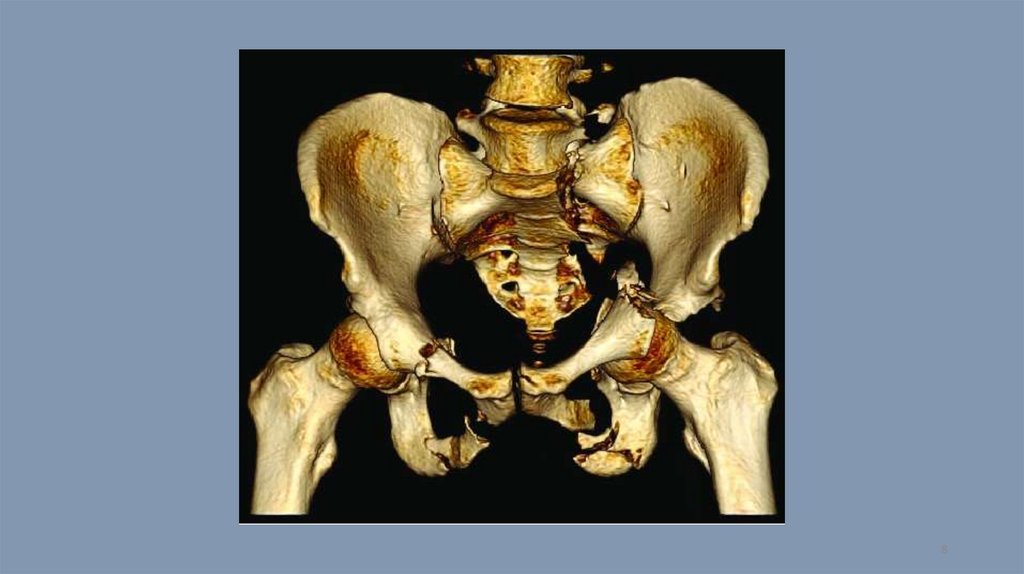

Компьютерная томография. Тест 14